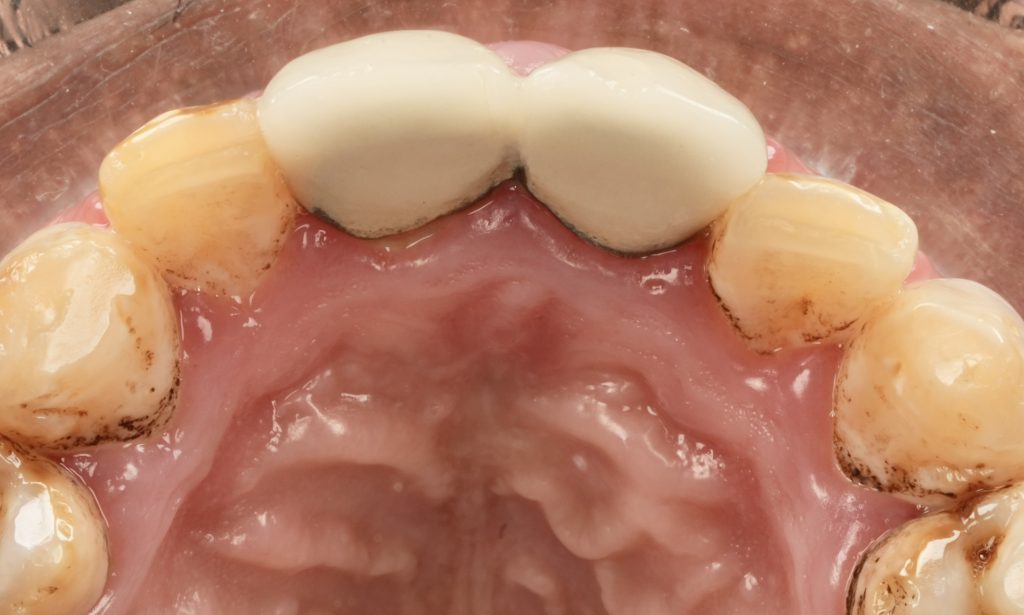

6️⃣ Finishing, Texture & Integration

Margins were refined using fine diamond strips, and surface gloss was enhanced with a multi-step polishing system (Shofu OneGloss + OptraPol Next Gen). Post-operative evaluation showed ideal incisal translucency, line-angle symmetry, and gingival health (Fig 5 & 6).